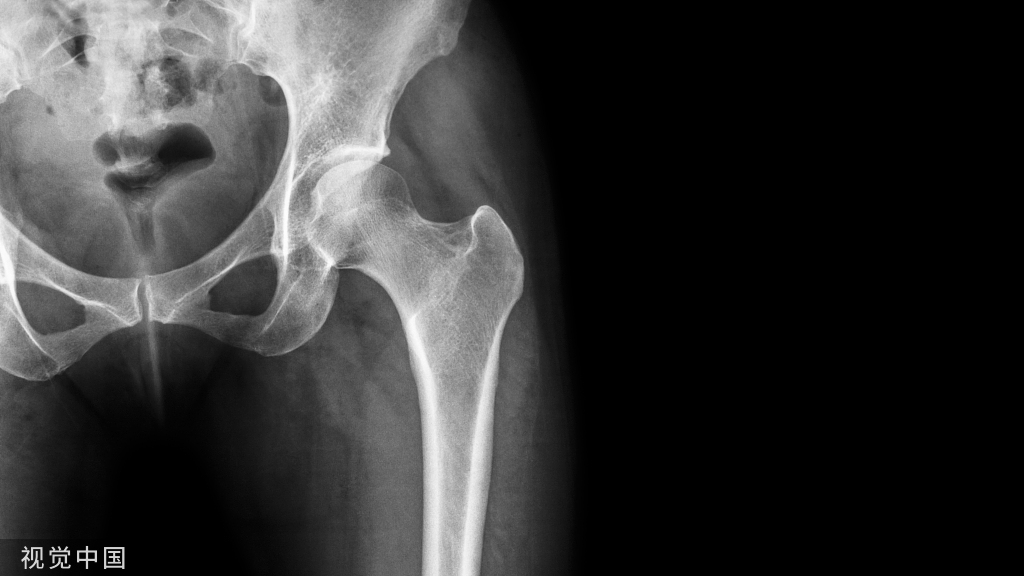

怀疑是足底筋膜炎引起疼痛的患者需要进行X线和MRI检查,以排除隐匿性骨性病变和肿瘤。足底筋膜炎在X线上无明显改变。

同位素骨扫描可以发现足底筋膜在内侧跟骨结节附着处摄取量增加,并可排除X线上难以显示的应力性骨折。